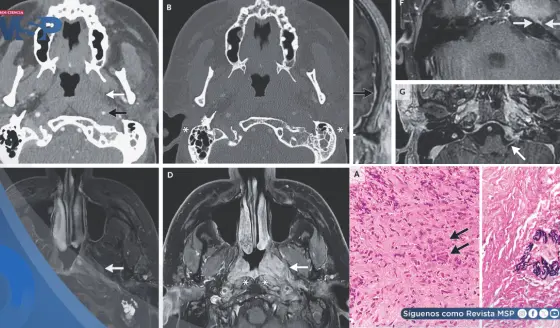

¿Dolor en mandíbula, oído o cabeza? Podría deberse a la articulación temporomandibular y no a migrañas